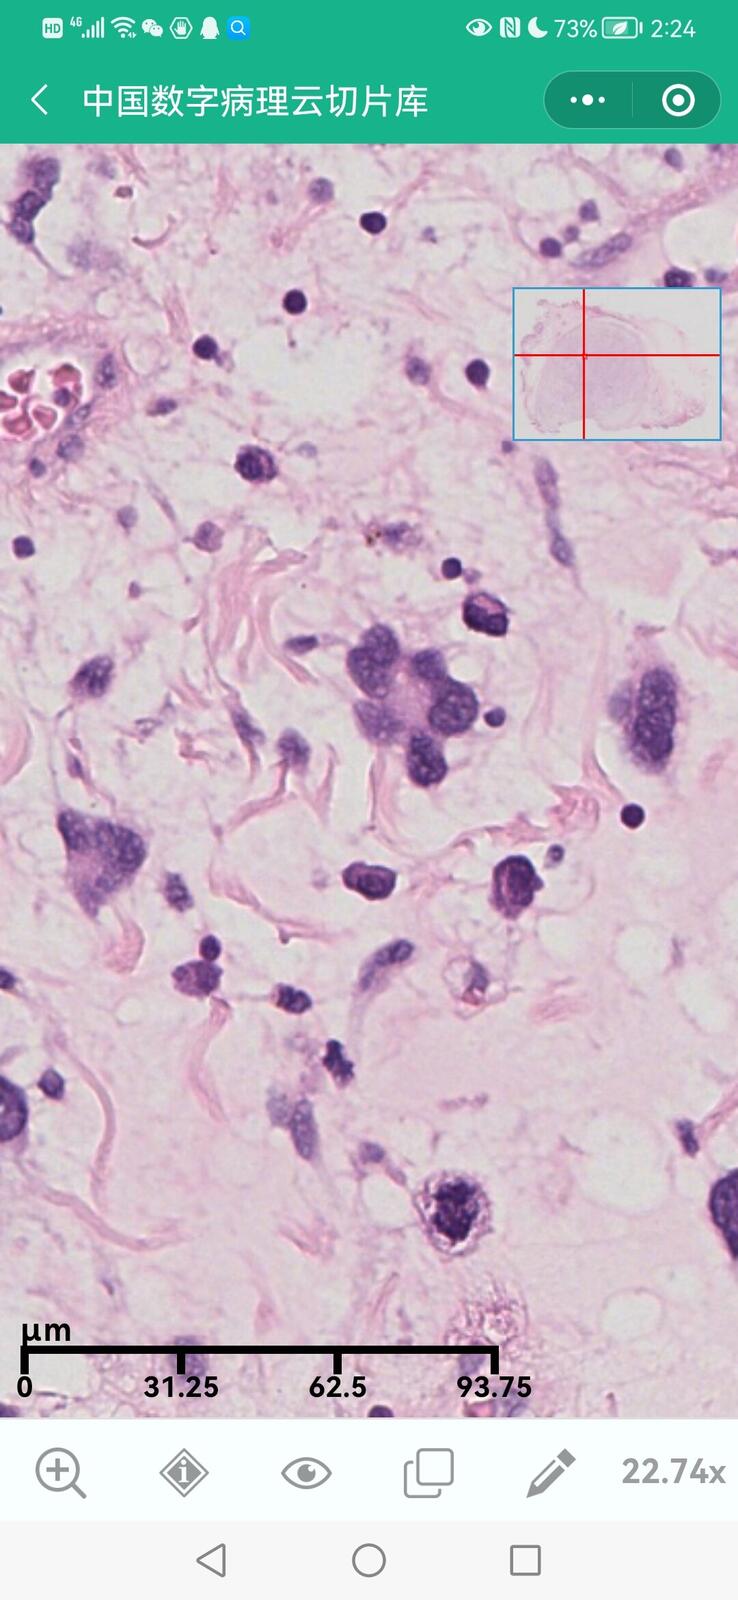

乳腺黏液性囊腺瘤伴导管内癌

乳腺多形性脂肪肉瘤

乳腺叶状囊肉瘤

乳腺分泌性癌(29岁)